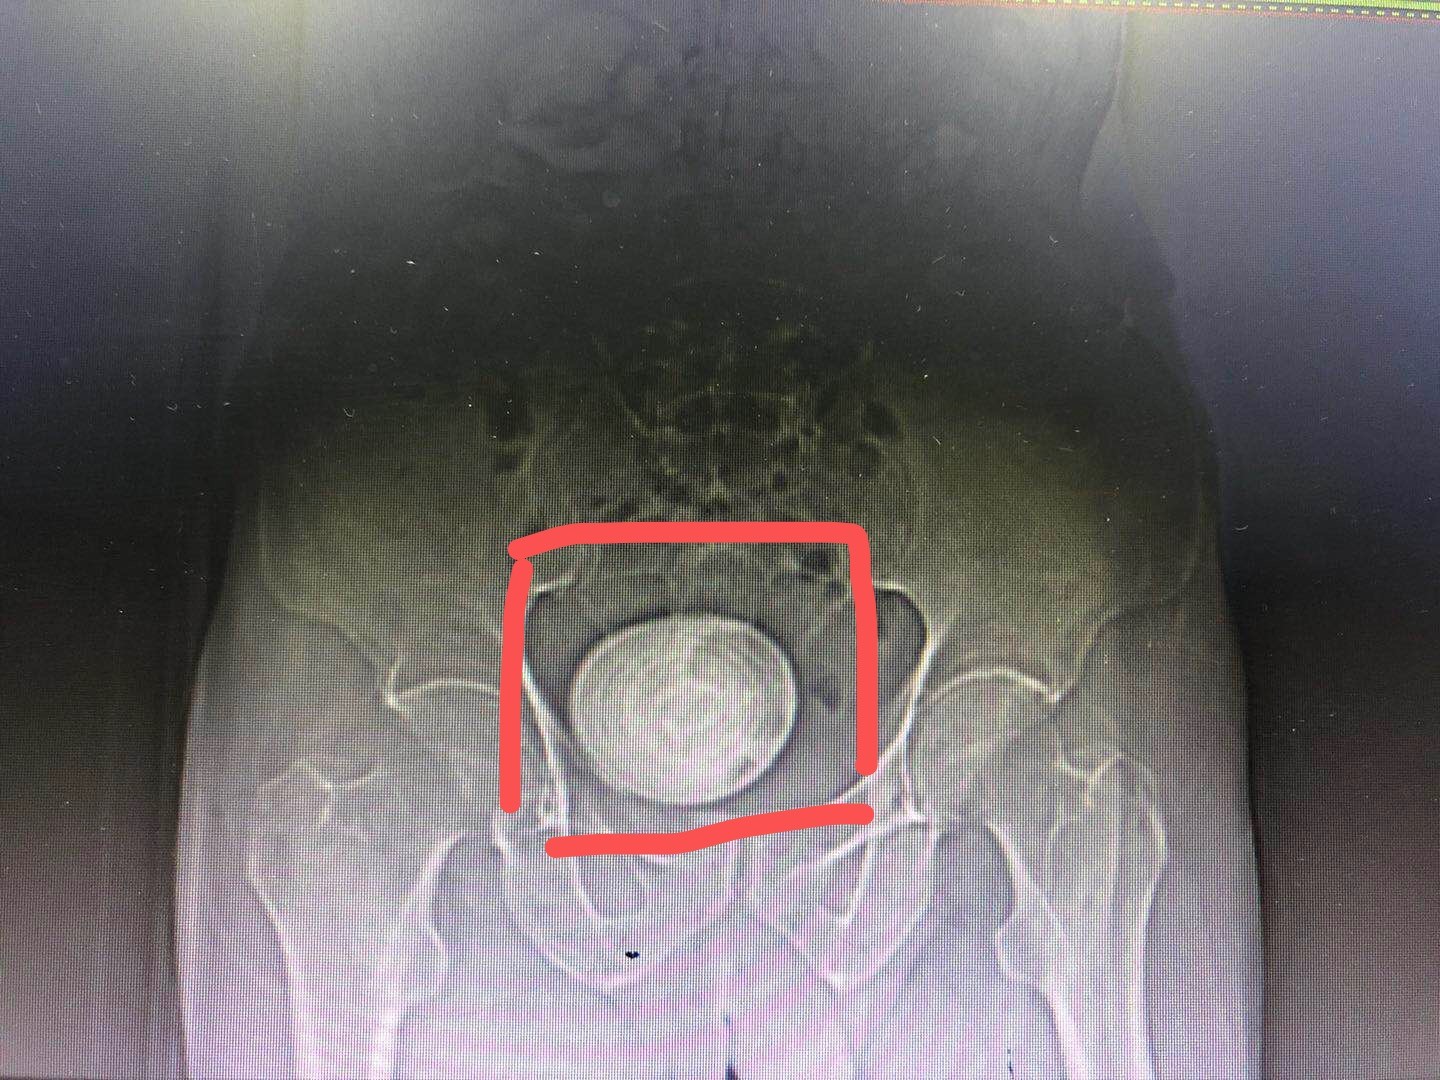

经过我们的认真检查,发现这位老人家膀胱内有一枚直径约8厘米的巨大结石,同时合并有前列腺增生的疾病。

经过术前准备,今日我们为这位老年男性患者顺利完成了膀胱切开取石手术,从膀胱内取出了这枚直径约8厘米的巨大结石,解除了老人家多年来的疾病困扰。

(5)X线检查可显示阳性膀胱结石阴影,阴性膀胱结石KUB不显影。